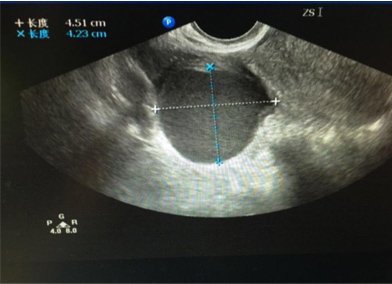

王女士,今年36岁,单位体检发现一侧卵巢有一直径约4cm大小的囊肿,没有什么不舒服,一听说有卵巢囊肿,王女士很紧张的来到我们妇科门诊就诊,问:“医生,我现在该怎么办?我这个囊肿会不会是癌症?需不需要马上就手术?……”

大部分卵巢囊肿都是卵巢排卵后卵巢修复过程中形成的,多随卵巢周期性变化而产生和消失,因此常见于生育年龄的女性。对于卵巢排卵,多数卵巢外观不会出现明显的变化,只有少数情况形成囊肿,一般形成的囊肿也不会太大,一般是一侧卵巢可见囊肿,我们临床医生称之为“生理性囊肿”,并且多数以5cm为界限,也有以8cm为界限。也就是说5cm之内的“生理性囊肿”,我们不需要采取任何措施,囊肿多数会自然消退,持续的时间长短因个人而异,有持续1个月或数月不等,通常会在三个月内自行消失。而对于超过5cm的囊肿,或持续存在,或变大,可能是病理性囊肿,比如卵巢囊性畸胎瘤、各种囊腺瘤,甚至少数是囊腺癌,因此这种情况下,我们建议手术治疗。